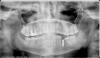

bani84 Опубликовано 22 апреля, 2011 Автор Поделиться Опубликовано 22 апреля, 2011 Подскажите, нормально ли вставили имплант?И вопрос про правую часть - два верхних зуба, что с ними можно сделать? В клинике говорят нада ставить коронки на них, а перед этим вылечить каналы. вот снимок Ссылка на комментарий

bani84 Опубликовано 5 мая, 2011 Автор Поделиться Опубликовано 5 мая, 2011 наконецто вставил фотку))) гляньте плиииз. Ссылка на комментарий